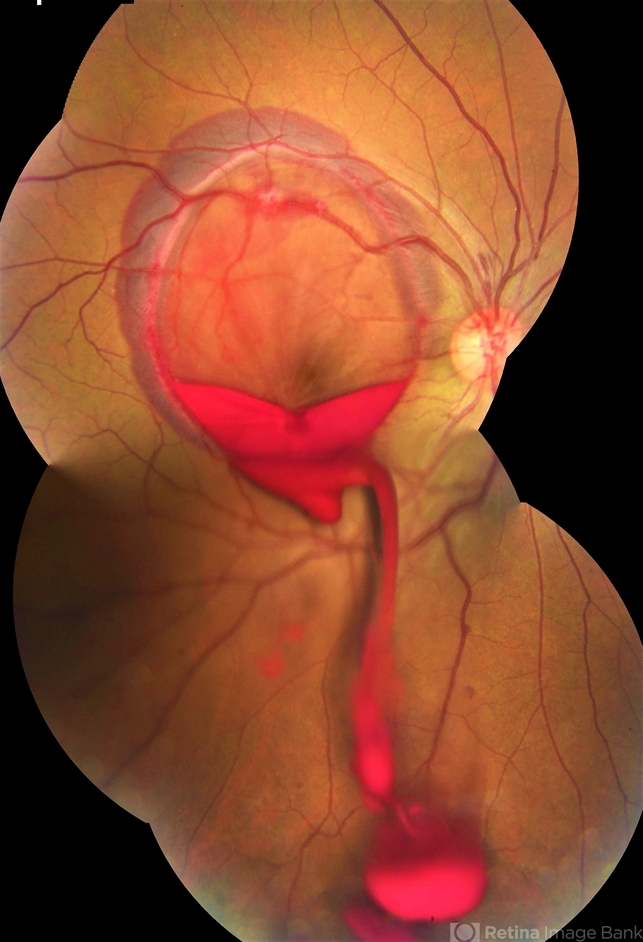

- valsalva retinopathy, subhyaloid hemorrhage

Topcon TRC-50 DX, Imaginet, 35 degree field. Flash 36 / Mosaic with four images. - Description

- Male patient, 23-years-old, with low visual acuity in the right eye. In the ocular examination of the retinography, intense subhyaloidal hemorrhage. 2 minutes after laser application.